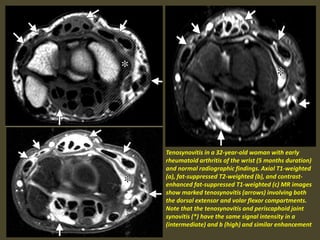

Tenosynovitis in a 32-year-old woman with early

rheumatoid arthritis of the wrist (5 months duration)

and normal radiographic findings. Axial T1-weighted

(a), fat-suppressed T2-weighted (b), and contrast-

enhanced fat-suppressed T1-weighted (c) MR images

show marked tenosynovitis (arrows) involving both

the dorsal extensor and volar flexor compartments.

Note that the tenosynovitis and periscaphoid joint

synovitis (*) have the same signal intensity in a

(intermediate) and b (high) and similar enhancement